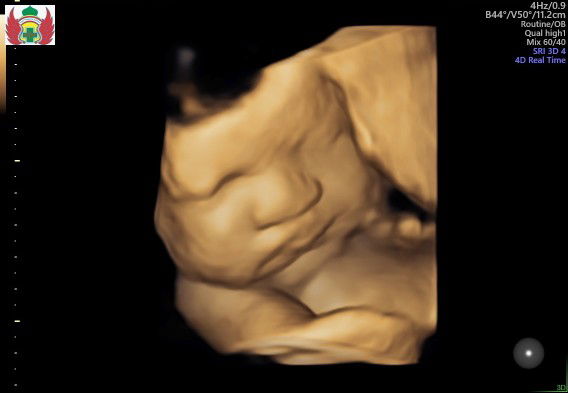

Ini usia 29wekk terakhir usg 4D. senin mau usg 4D lagi usia 34week perkiraan

32week dede malu muka nya di tutupin mulu

Terakhir usg 4d uk 36-37week😍👶🏻

Ak usg 4d usia kehamilan ak 31 week bun